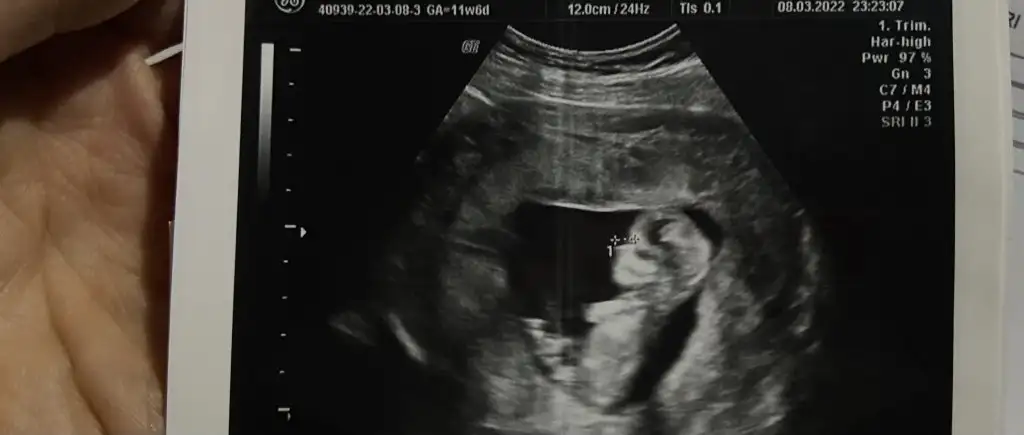

Sata göre 12+2 ama 12+5 çıktı canım ahahhaha bende çok şaşırdım canım pipişeKuzum gerçekten pipi çok net

12+5 çıktı canımAy nasıl bariz belli canım. Sağlıkla doğsun inşallah.Senin bugün kaç hafta kaç günlüktü bende cumartesi gidicem inşallah tahmin yapar banada İkili test için kan verdin mi ense ölçümü falan yaptı mi?